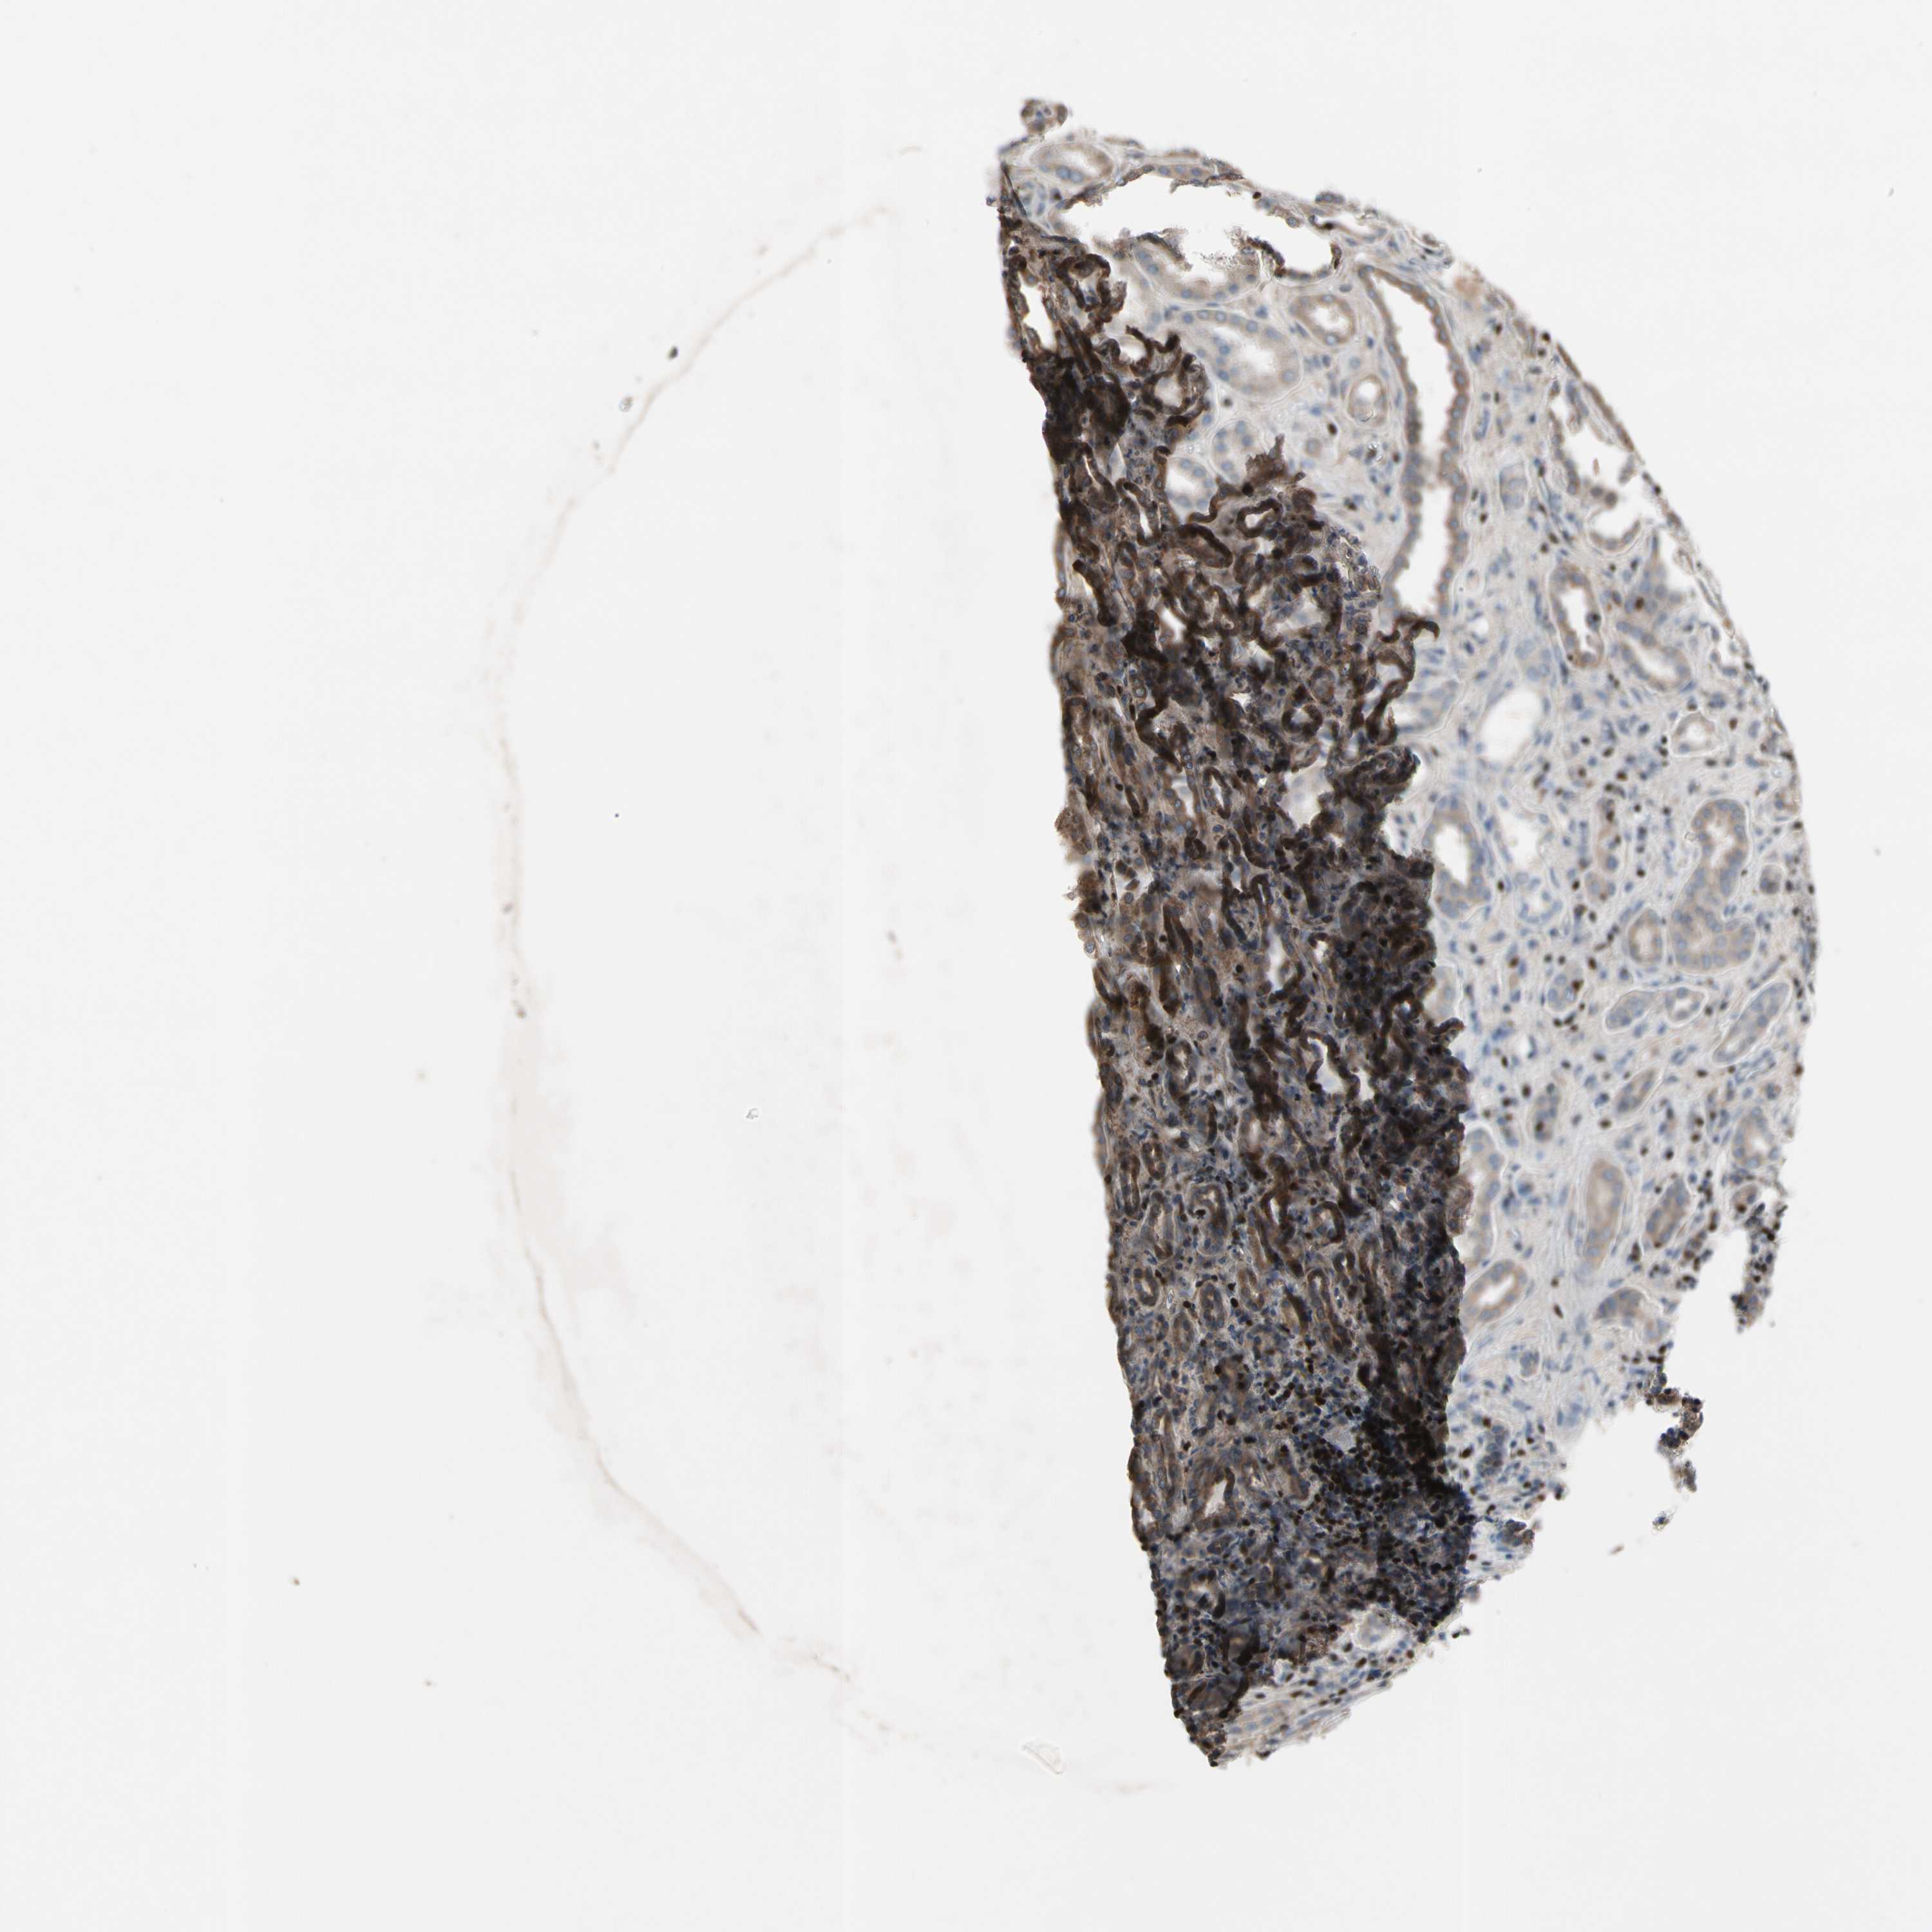

Information about each individual sample is listed below, including gender, age, a tissue section image and estimated fractions of cell types. pTPM (transcripts per million) values give a quantification of the gene abundance which is comparable between different genes and samples.

Female, age 67

Kidney sample 56 pTPM: 0.3

Cells in tubules: 60 Cells in glomeruli: 20 Fibroblasts: 5 Other cell types: 15